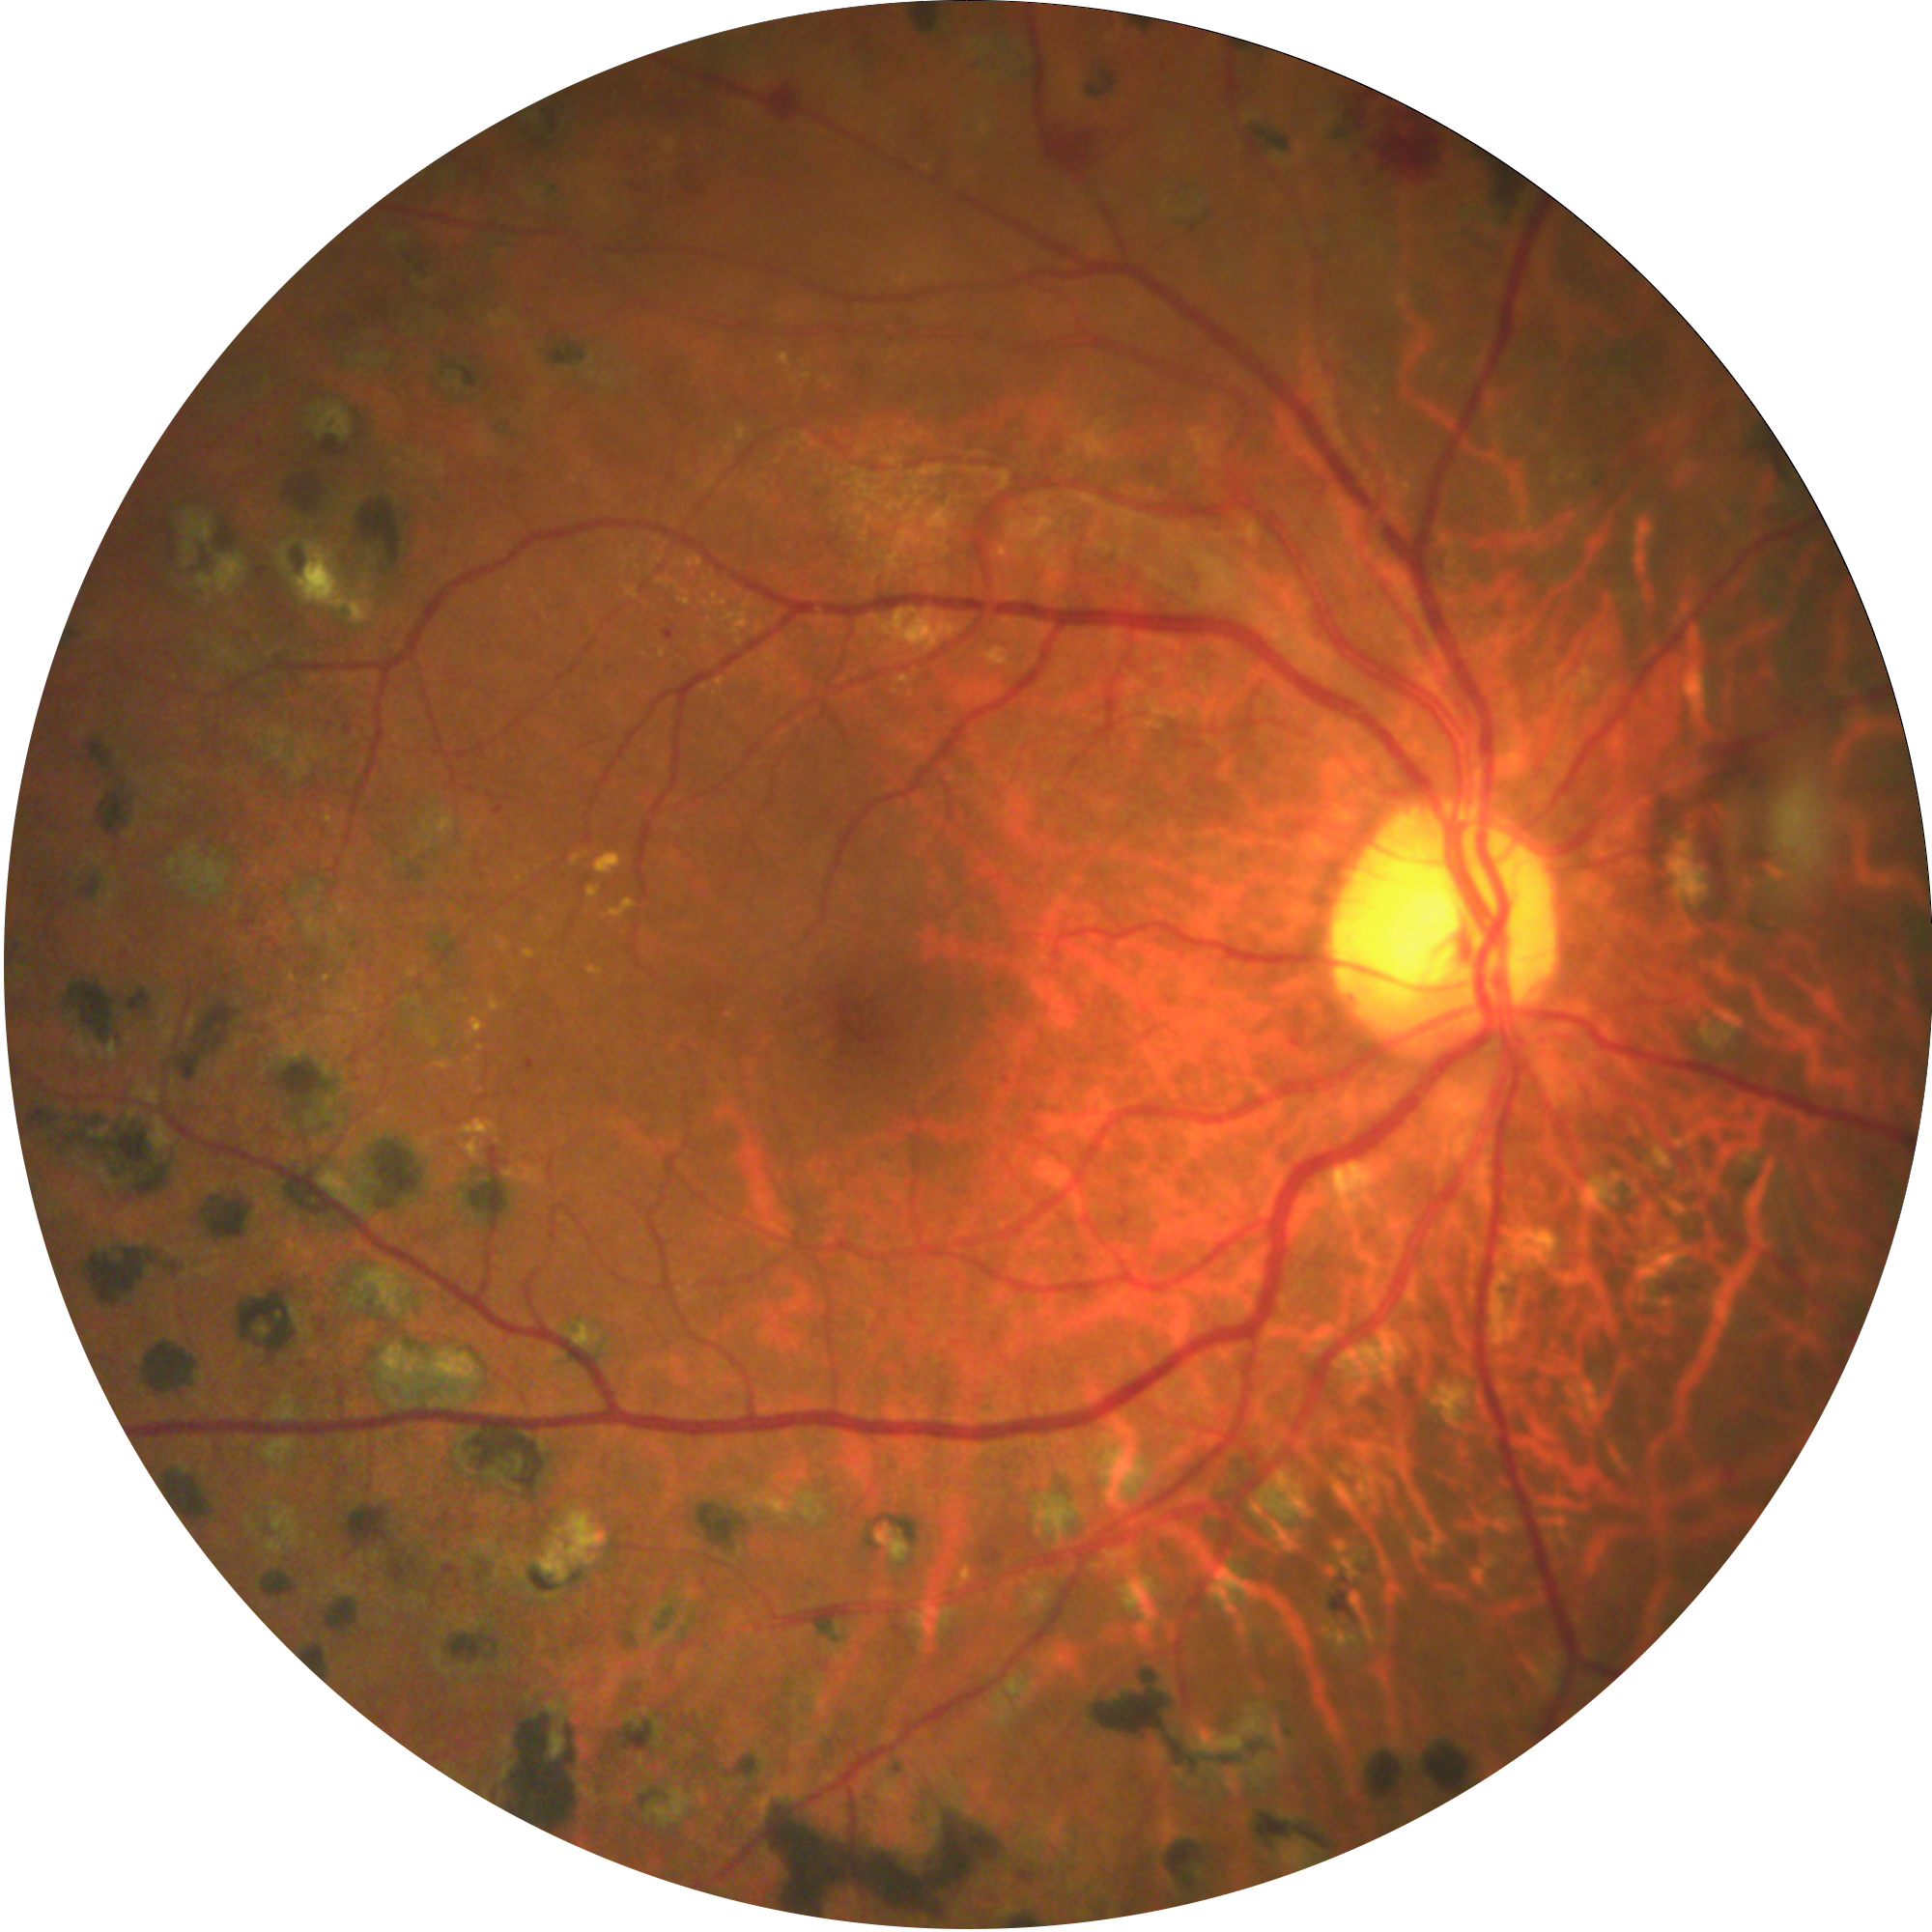

Delivering crystal-clear, high contrast retinal images with a 45° field of view in single shot, and montage to reach the periphery.

Providing retinal images with 2 different imaging modalities

We know that diabetic retinopathy(DR) is one of the leading causes of preventable blindness. That is why we developed our own AI algorithm to automatically detect signs of DR in the retina. This makes it so much more easier to screen and refer for a DR patient.

TrueColor, Red-Free Retinal Imaging